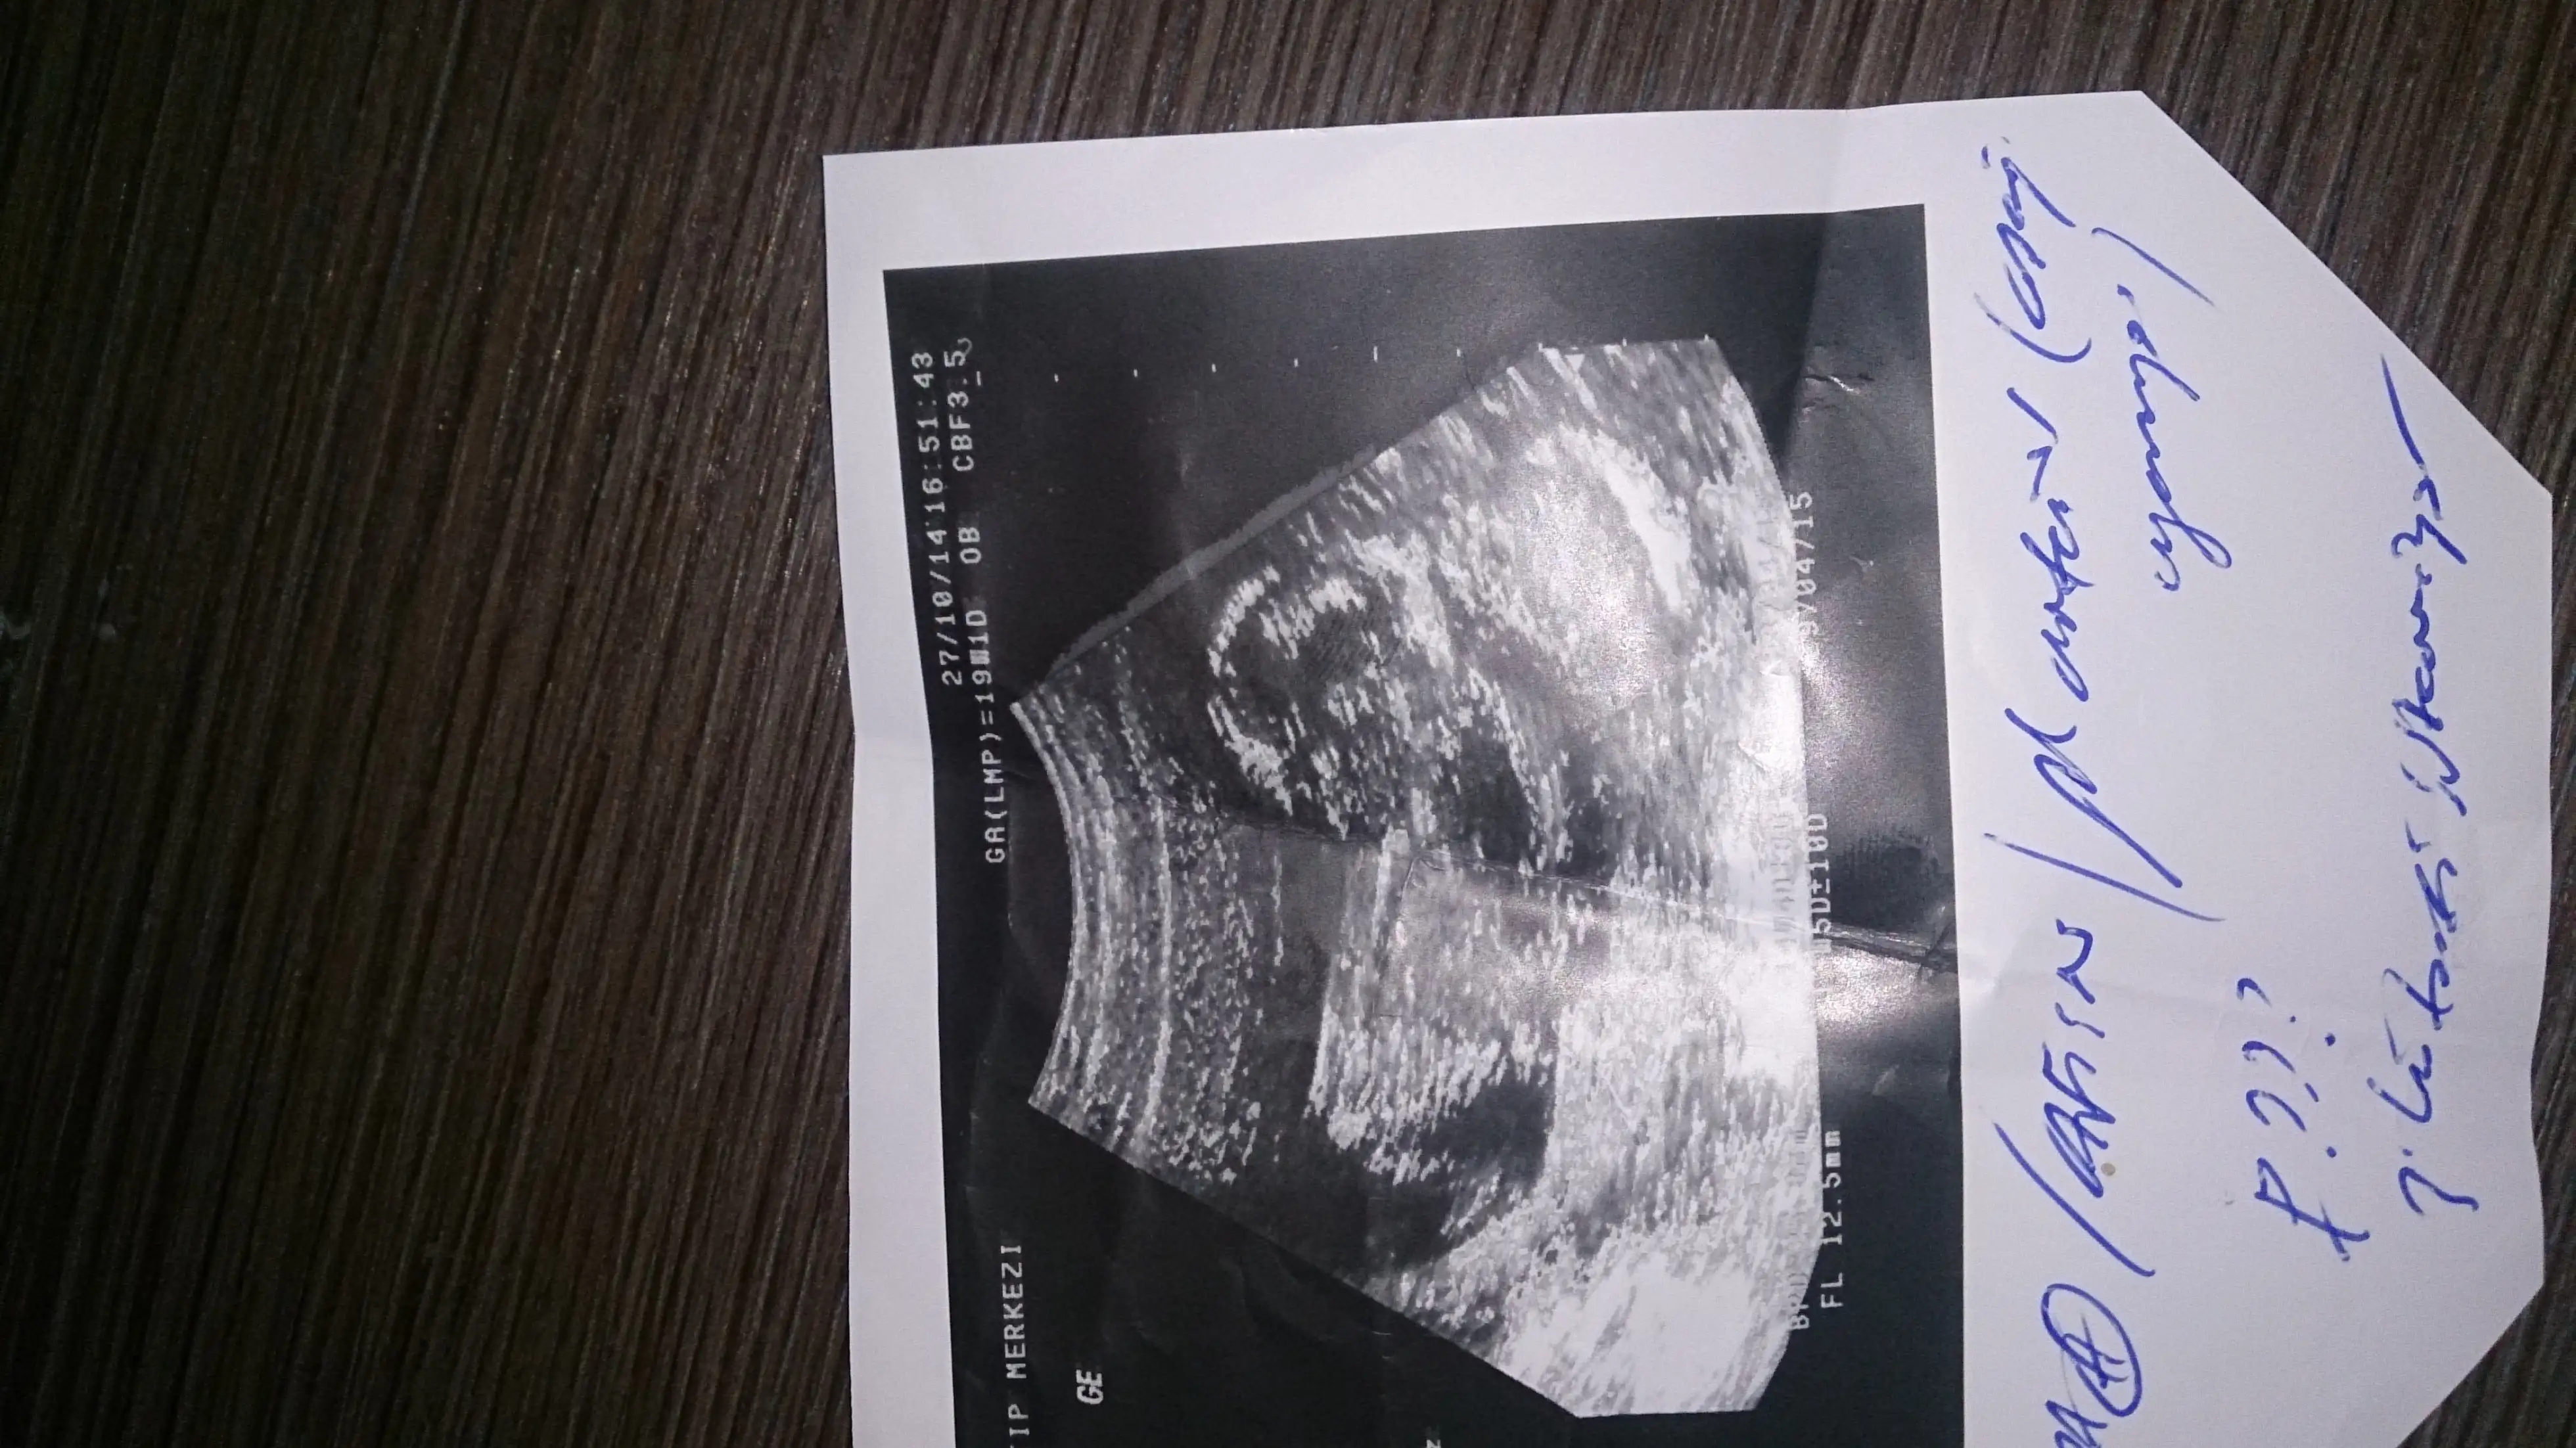

Size yorum yaptimmi bilmiyorum ama kız olabilir bebisiniz bazı arkafaslarinki gorunmuyo resimleri telden giriyorum oyuzden acmiyo fotolarKizlar benim onceki gonderime sagolsun hcan86 arkadas yorum yapti ama bu isi anlayabilen diger arkadaslarda yorum yapabilirler mi acaba?

Anladigim kadariyla bana kiz gibi geldi.Bana da yorum

Goruntuler pek net degil yani nub cikintisini goremedimKızlar ne olur bana bi yorum yapın ya herkese yaptınız bi bana yapmadınız